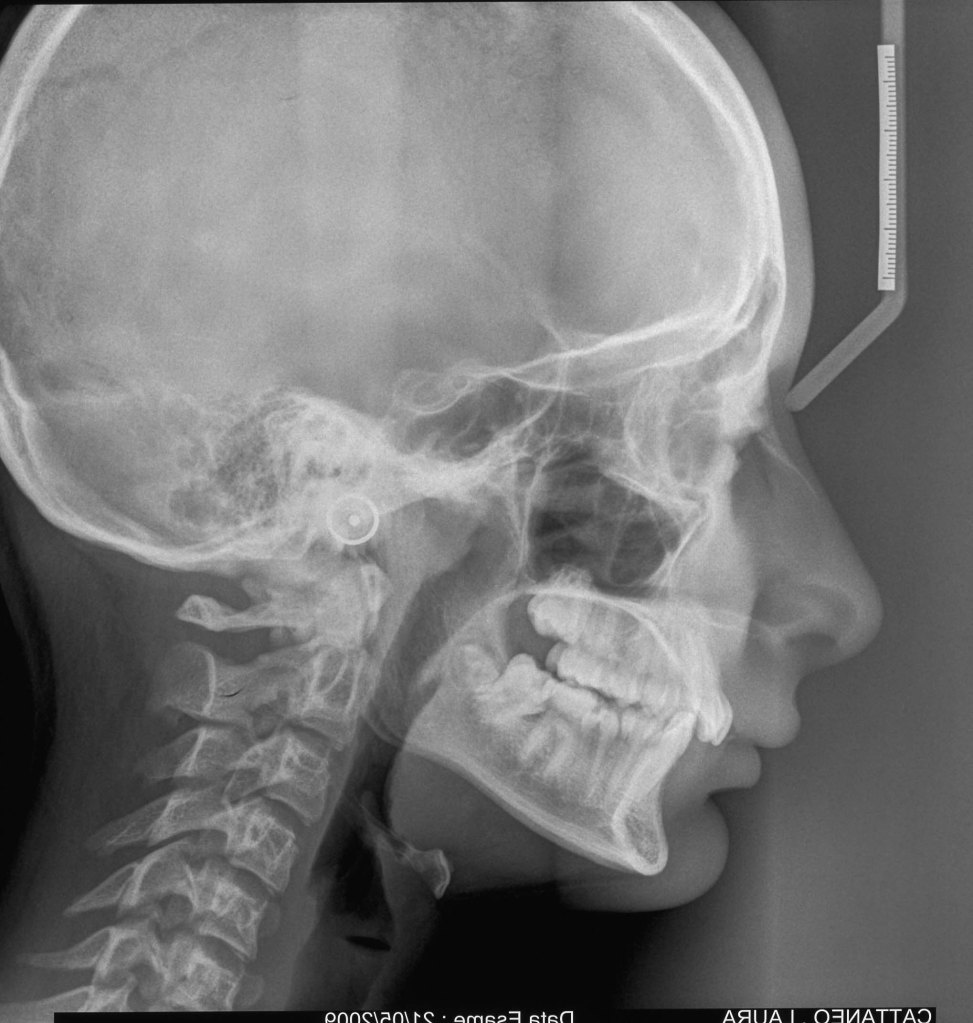

TELERADIOGRAFIA DEL CRANIO

La teleradiografia del cranio è una radiografia della testa da cui si ottiene un’immagine su cui è possibile effettuare misurazioni precise delle diverse strutture e caratteristiche del cranio (l’analisi cefalometrica). È uno studio che può affiancare la panoramica dentaria preliminare ai trattamenti ortodontici. Può essere eseguita da tre angolazioni (latero-laterale, postero-anteriore e assiale), ma quella più utilizzata per l’analisi cefalometrica è la proiezione latero-laterale.

La teleradiografia del cranio consente all’odontoiatra di avere una visione d’insieme dell’anatomia della testa per capire se la posizione reciproca delle arcate dentarie è corretta e se i denti sono nella giusta posizione rispetto alle ossa. Permette quindi di pianificare interventi correttivi in caso di problemi come malocclusioni e morsi inversi, e nel caso dell’analisi secondo la proiezione postero-anteriore, di visualizzare frontalmente l’intero cranio per rilevare eventuali asimmetrie.

Al paziente viene fatto indossare un grembiule di piombo per schermare il resto del corpo dalle radiazioni. Dopo di che, il paziente viene fatto posizionare in piedi all’interno di un apparecchio chiamato craniostato, che grazie a due prolungamenti che si vanno a inserire ciascuno in un orecchio, consentono di assumere la posizione corretta e di mantenerla per tutta la durata dell’analisi. Lo sguardo deve essere orientato in avanti, i denti stretti e le labbra morbide. Per raggiungere la postura più corretta il paziente può essere invitato a deglutire e a mantenere le arcate dentarie nella posizione raggiunta. A questo punto non resta che rimanere immobili per 8-15 secondi, fissando l’orizzonte.